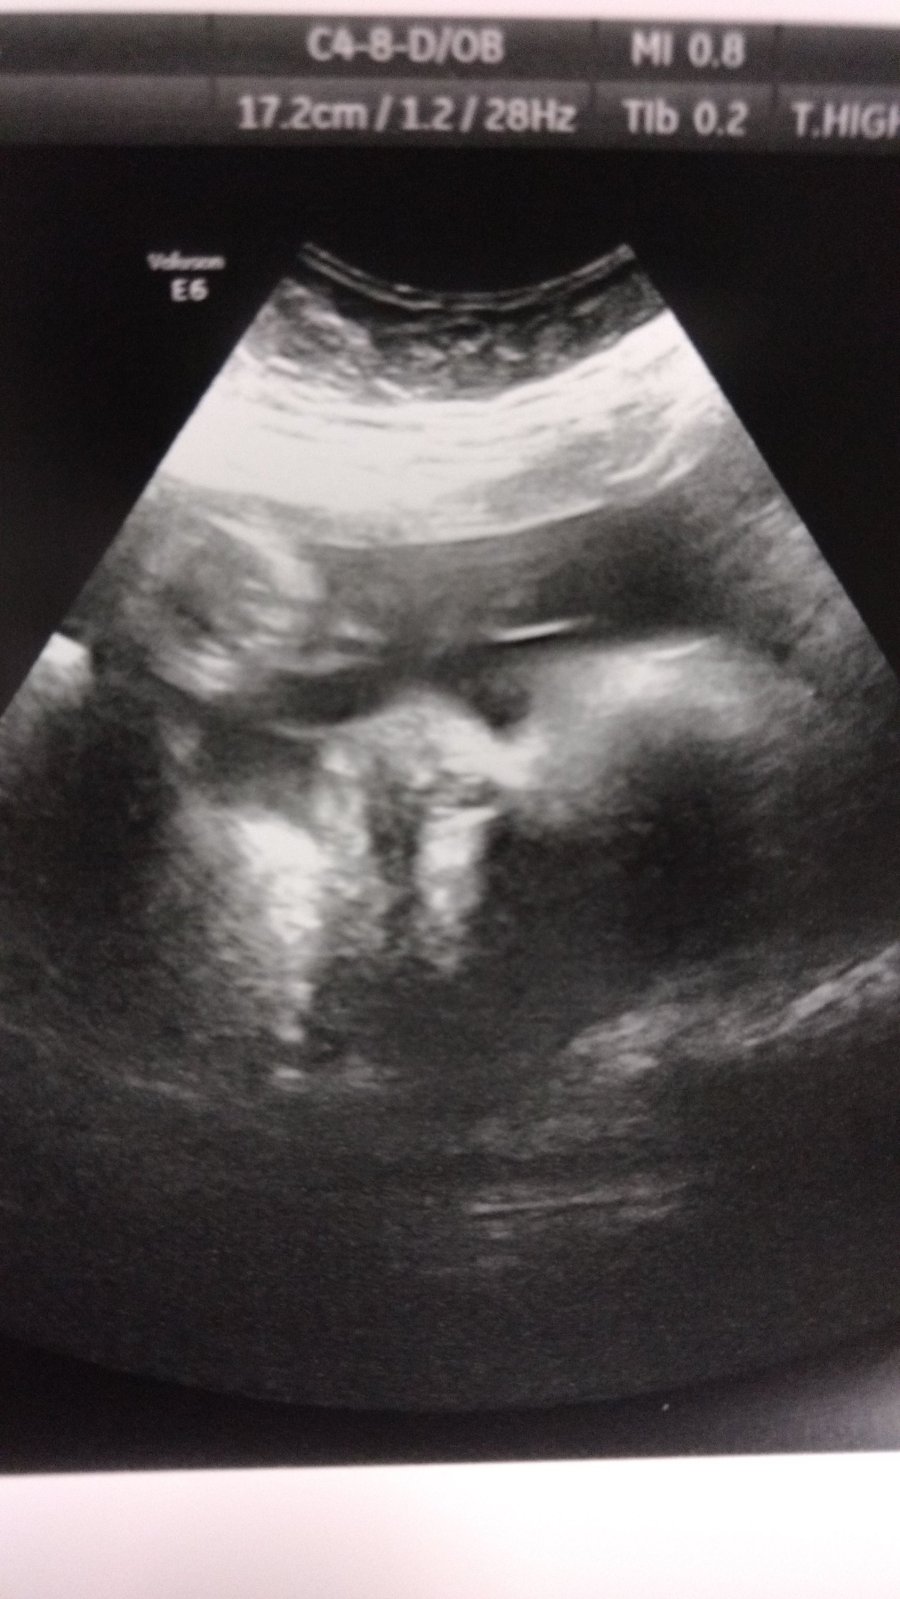

We finally got a “oh look, a baby!” Ultrasound photo this past week, which was nice to see.

Hi Baby Zora! Thanks for the wave and finally showing us your tiny face.